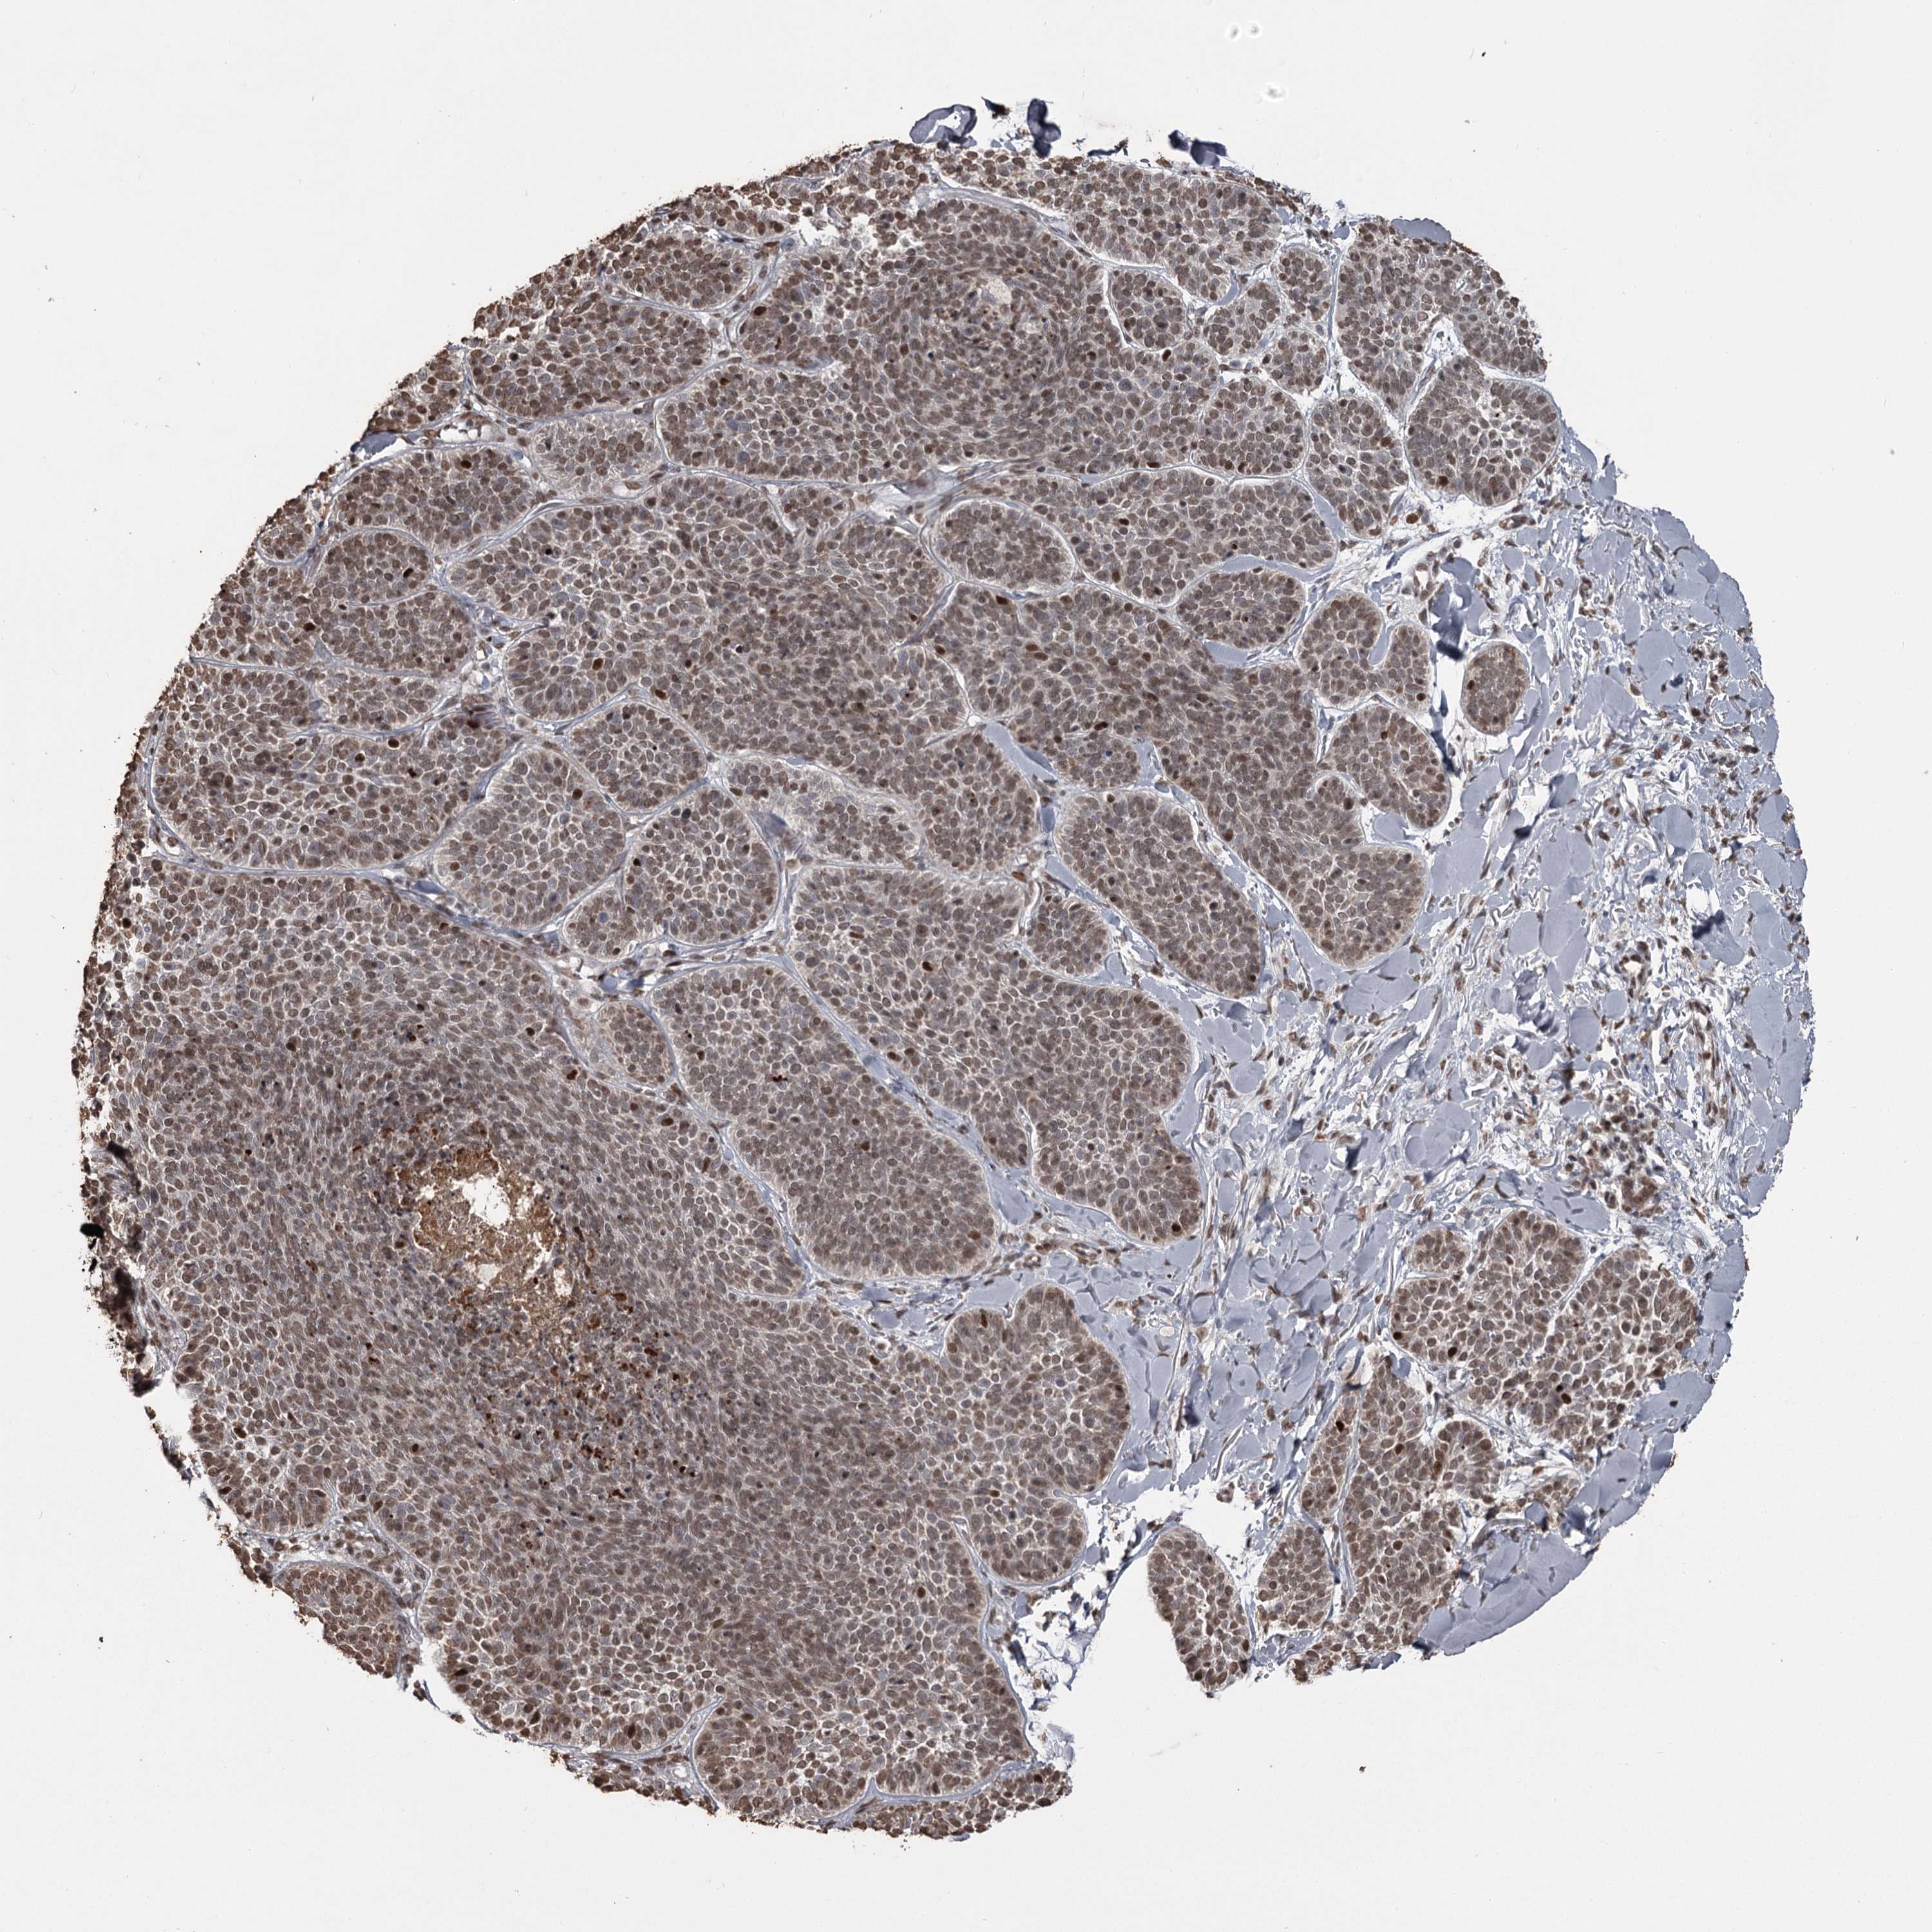

SKIN CANCER - Protein expressioni

A mouse-over function shows sample information and annotation data. Click on an image to view it in a full screen mode. Samples can be filtered based on level of antibody staining by selecting one or several of the following categories: high, medium, low and not detected. The assay and annotation is described here.

Antibody stainingi

Antibody staining in the annotated cell types in the current human tissue is reported as not detected, low, medium, or high, based on conventional immunohistochemistry profiling in selected tissues. This score is based on the combination of the staining intensity and fraction of stained cells.

Each image is clickable and will lead to virtual microscopy that enables deeper exploration of all samples and also displays staining intensity scores, fraction scores and subcellular localization as well as patient and tissue information for each sample.

Antibody HPA038732

Antibody HPA038733

Staining

High

Medium

Low

Not detected

Intensity

Strong

Moderate

Weak

Negative

Quantity

>75%

75%-25%

<25%

None

Location

Nuclear

Cytoplasmic/membranous

Cytoplasmic/membranous,nuclear

Basal cell carcinoma

Squamous cell carcinoma, NOS

Squamous cell carcinoma, metastatic, NOS